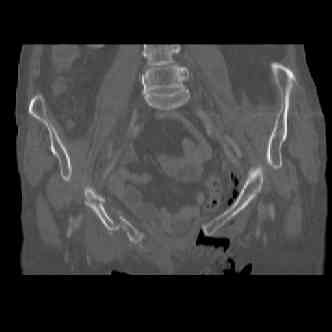

attached are several CT cuts. please let me know if you need more. the CT is pre-pelvic ex-fix placement.

Имя     : image007.jpg